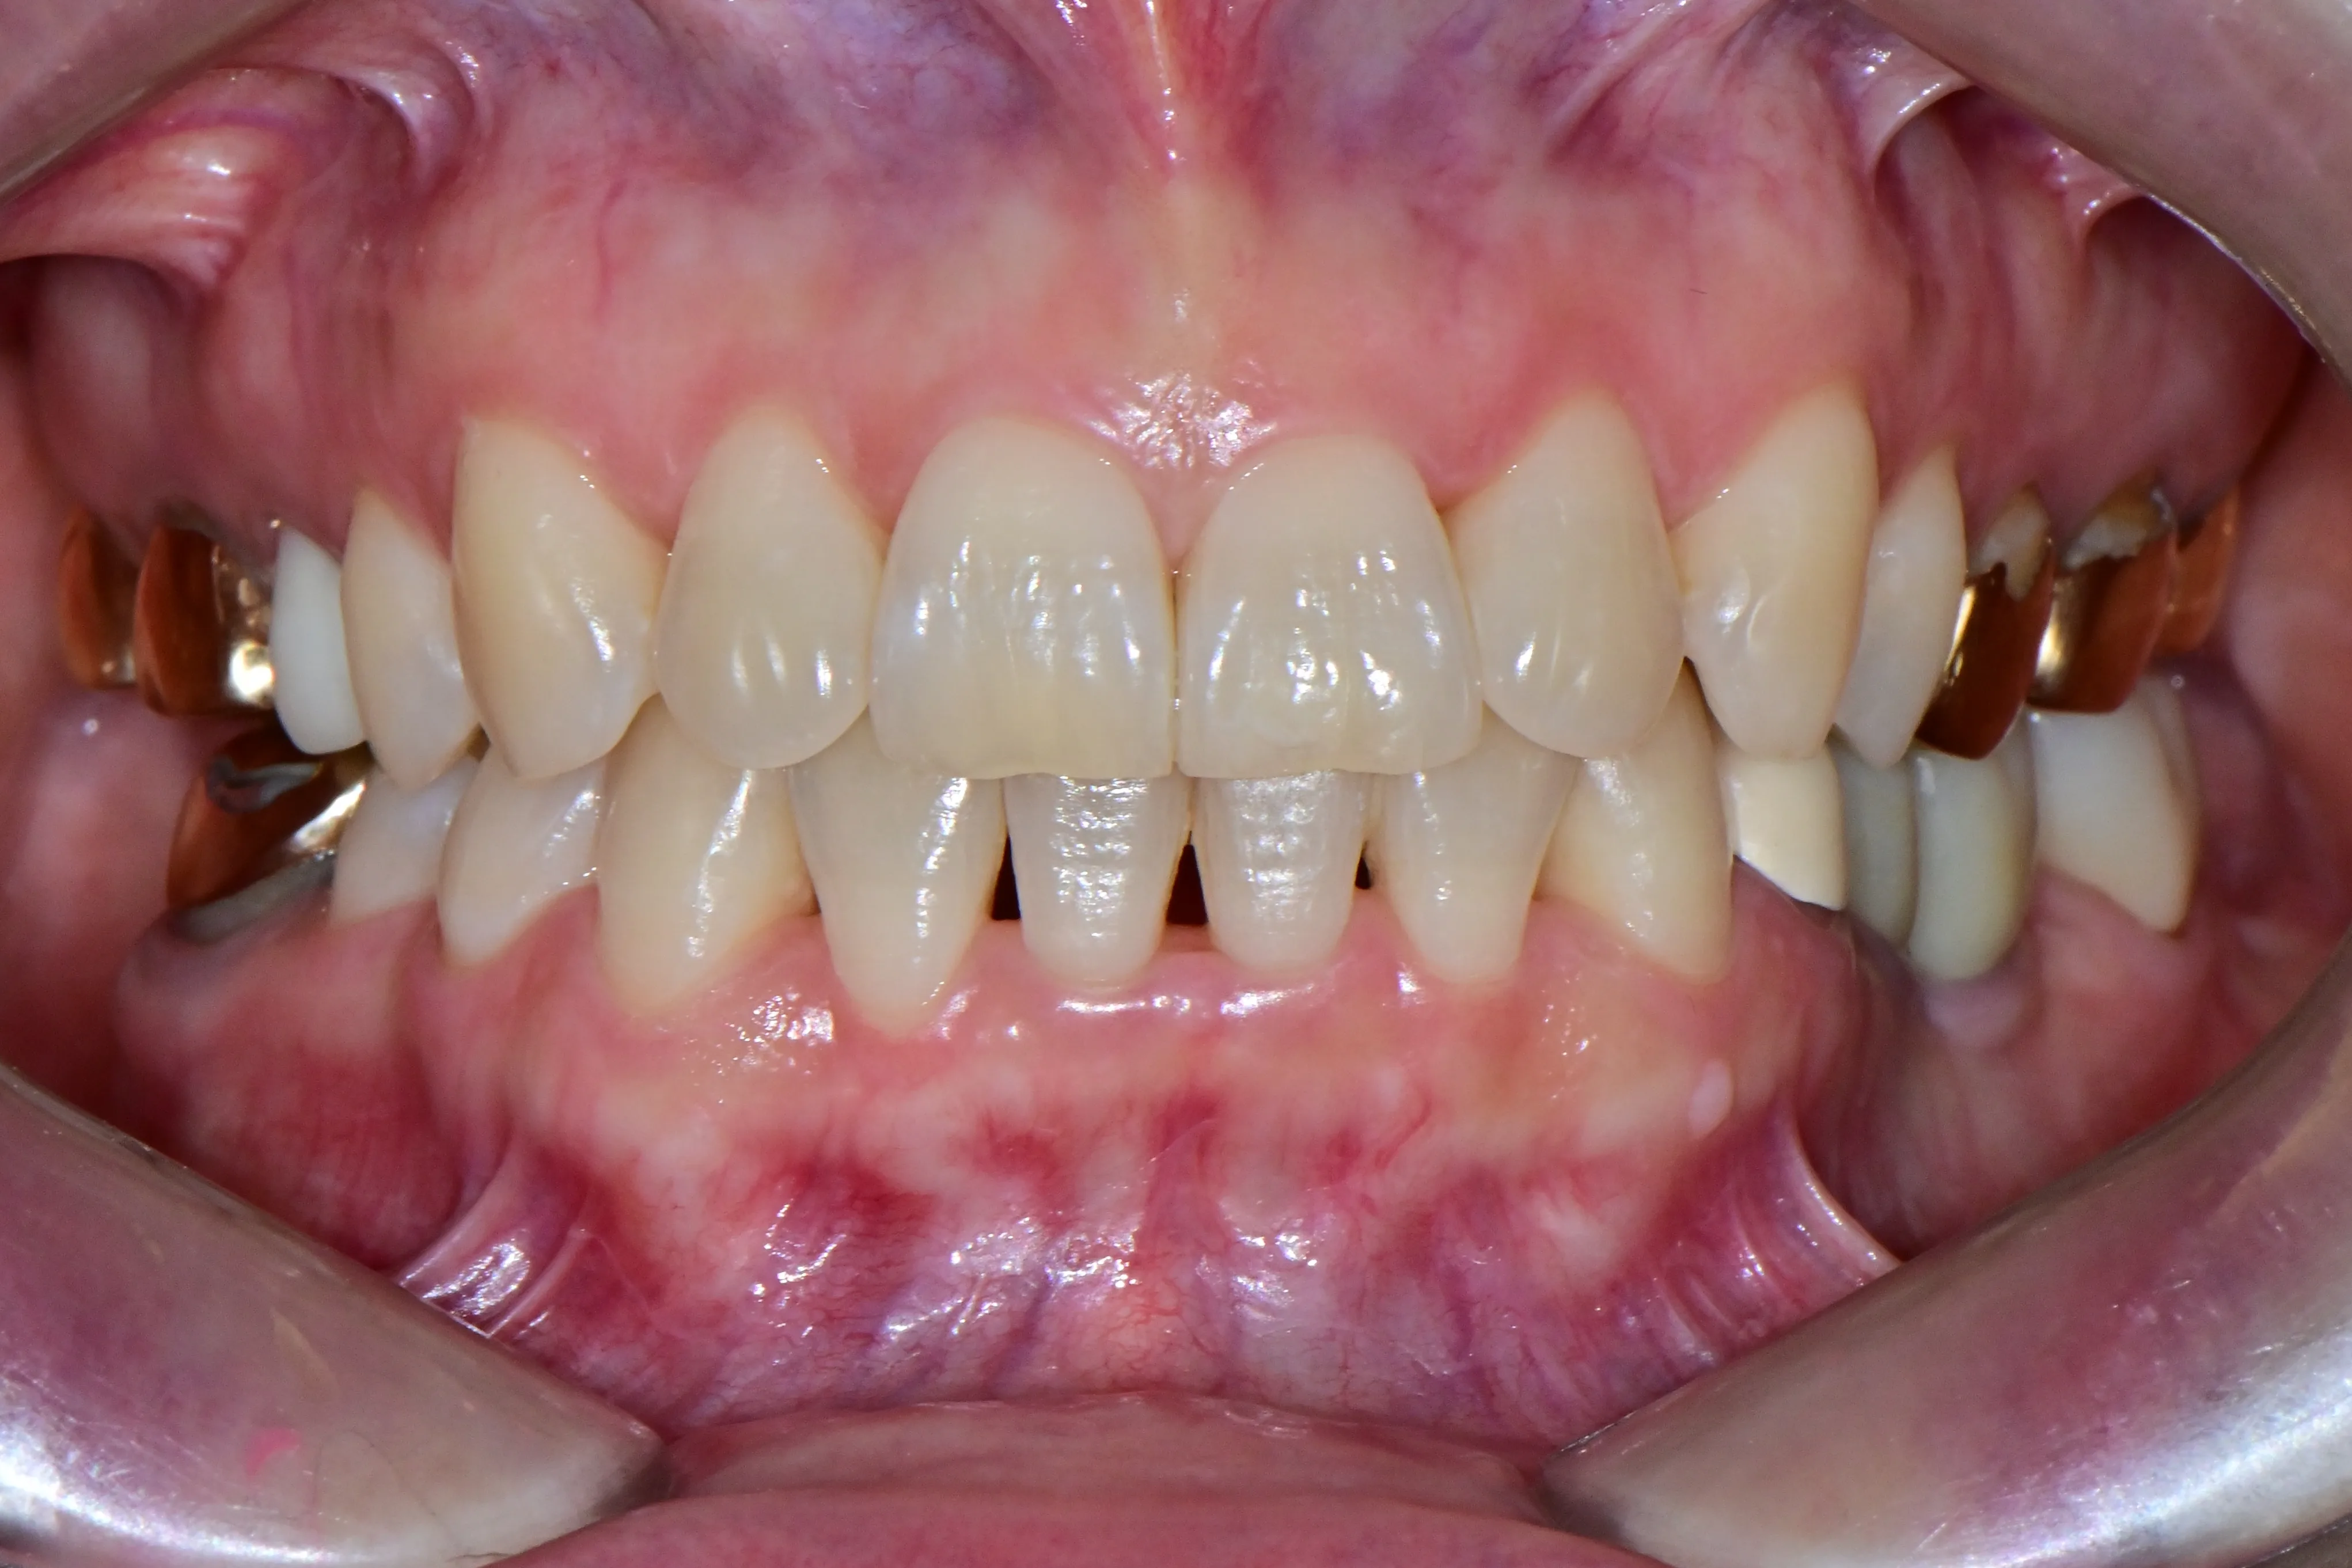

이 환자분은 이미 구강 안에 여러 개의 임플란트와 브릿지 보철물이 있는 상태였습니다. 앞니는 가지런하지 않고, 윗니가 아랫니를 깊게 덮는 과개교합(deepbite)도 있었습니다. 이런 경우 가장 중요한 것은 기존 임플란트와 보철물의 교합을 그대로 유지하면서, 나머지 치아만 가지런하게 배열하는 것입니다.

인비절라인의 디지털 치료 계획을 활용해서, 임플란트와 보철물이 있는 어금니는 움직이지 않도록 고정하고 앞니 위주로만 이동시켰습니다. 덕분에 발치 없이, 고무줄이나 미니스크류 같은 추가 장치 없이도 15개월 만에 치료를 마무리할 수 있었습니다.

보철물이나 임플란트가 많다고 교정이 어려운 것은 아닙니다. 오히려 이를 고정원으로 활용하면 치료 효율이 높아지는 경우도 있습니다.